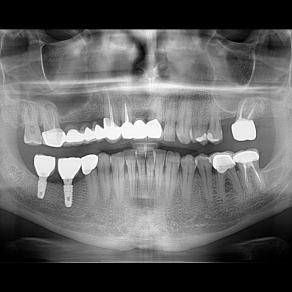

İmplant etrafındaki kemik açıklığını kemik grefti ile tedavi ettiğimiz vakamız